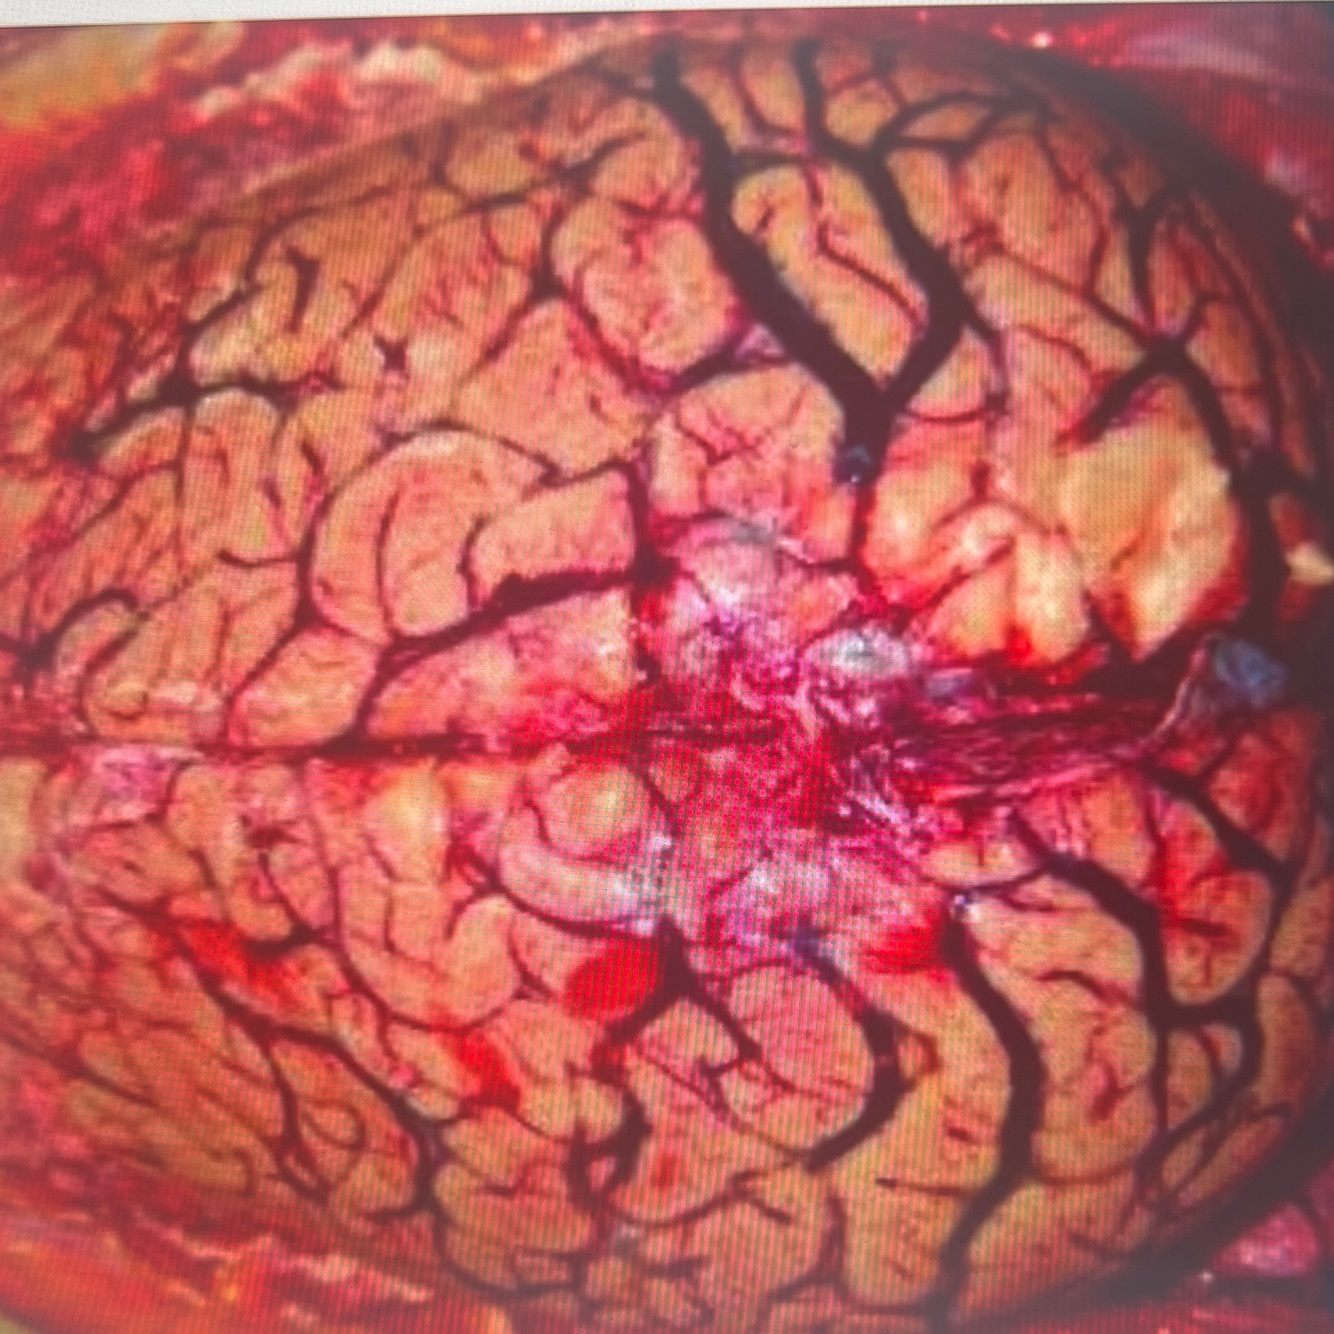

Diagnosis: intracerebral hemorrhage

Location: basal ganglia

A coronal section in the brain showing a localised area of large dark red brown hematoma in the cerebral hemisphere

Note compression effects on the ventricle

Smaller hemorrhagic foci are also seen